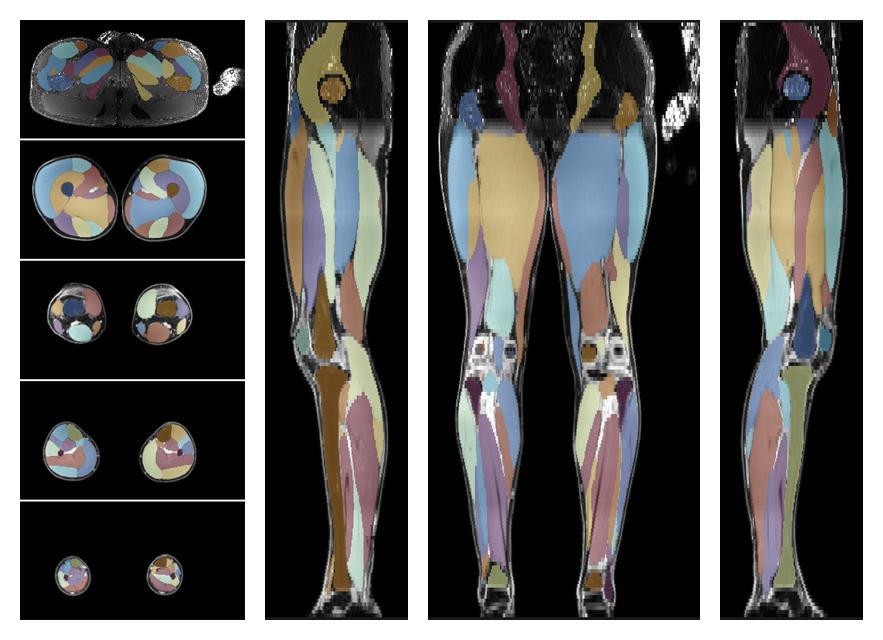

• Automated muscle and bone segmentation.

Overlay of automated muscle segmentation labels on dixon water image.

• 3D volume render of automated muscle segmentation.

3D render of automated muscle segmentation labels generated using a CNN UNET.